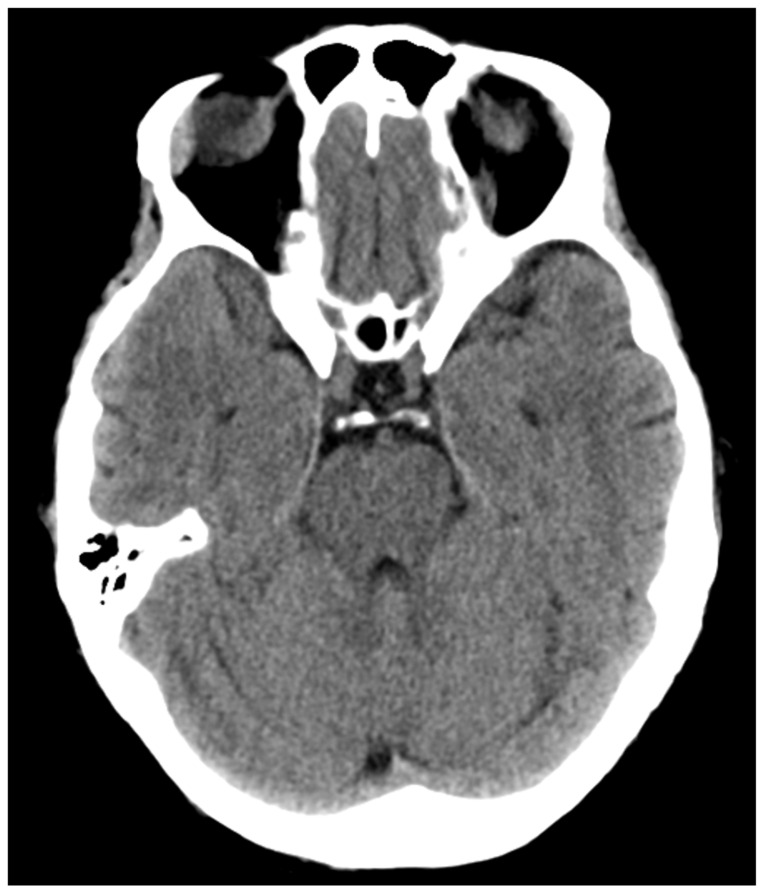

Introduction: Posterior reversible encephalopathy syndrome (PRES) is an illness in which a person can present with acutely altered mentation, drowsiness or sometimes stupor, visual impairment, seizures (focal or general tonic-clonic), and sudden or constant, non-localized headaches.1 Patients at risk for developing PRES include those with underlying hypertension, preeclampsia, kidney disease, liver disease, exposure to cytotoxic medications or immunosuppressants, autoimmune disorders or sepsis. As a syndrome, PRES has gone underdiagnosed given its broad symptomatology. While it appears to affect people of all ages, it is more commonly found in middle-aged females. The underlying cause for PRES remains unclear, but some proposed mechanisms center on the dysregulation of cerebral autoregulation, the brain's ability to maintain constant cerebral blood flow over a range of blood pressures via the constriction or dilation of the cerebral blood vessels.2 The treatment for PRES includes management of hypertension as well as diagnosing and treating the underlying etiology. This disease process needs to be recognized early by the emergency provider to reduce mortality.Eclampsia and other hypertensive disorders in women affect as many as 10% of all pregnancies worldwide and are responsible for approximately 10% of all maternal deaths in the United States.3 Eclampsia is defined as new onset seizures in a woman with a history of preeclampsia who is between 20 weeks gestation and within four weeks postpartum.4 As an emergency medicine provider, it is imperative to be able to manage and treat a patient with eclampsia to decrease mortality and morbidity of the mother and fetus. Management of eclampsia includes treatment for seizures using magnesium sulfate, treatment for hypertension, and emergent obstetrics consult for possible delivery of the fetus.4.

Educational objectives: At the end of this oral boards session, examinees will be able to: 1) demonstrate familiarity with the structured interview oral board format and case play; 2) recognize the history and exam features concerning for PRES and eclampsia; 3) order appropriate diagnostic workup for postpartum and hypertensive emergencies including eclampsia and PRES; 4) understand treatment options for the management of eclampsia (intravenous [IV] magnesium sulfate, IV antihypertensive therapy, and emergent consultation with an obstetrician [OB/GYN]); 5) understand threshold for taking control of airway in patients with eclampsia; 6) understand indications for ordering brain imaging in patients with eclampsia and altered mental status; and 7) demonstrate effective communication with treatment team/family members as well as correct disposition of the patient to a higher level of care (intensive care unit [ICU]).